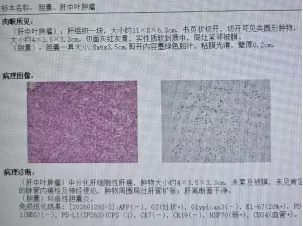

手术过程平稳顺利,全程仅用时4小时,出血量仅约200ml。术后病理结果确诊为肝细胞癌,切缘阴性,实现了根治性切除。